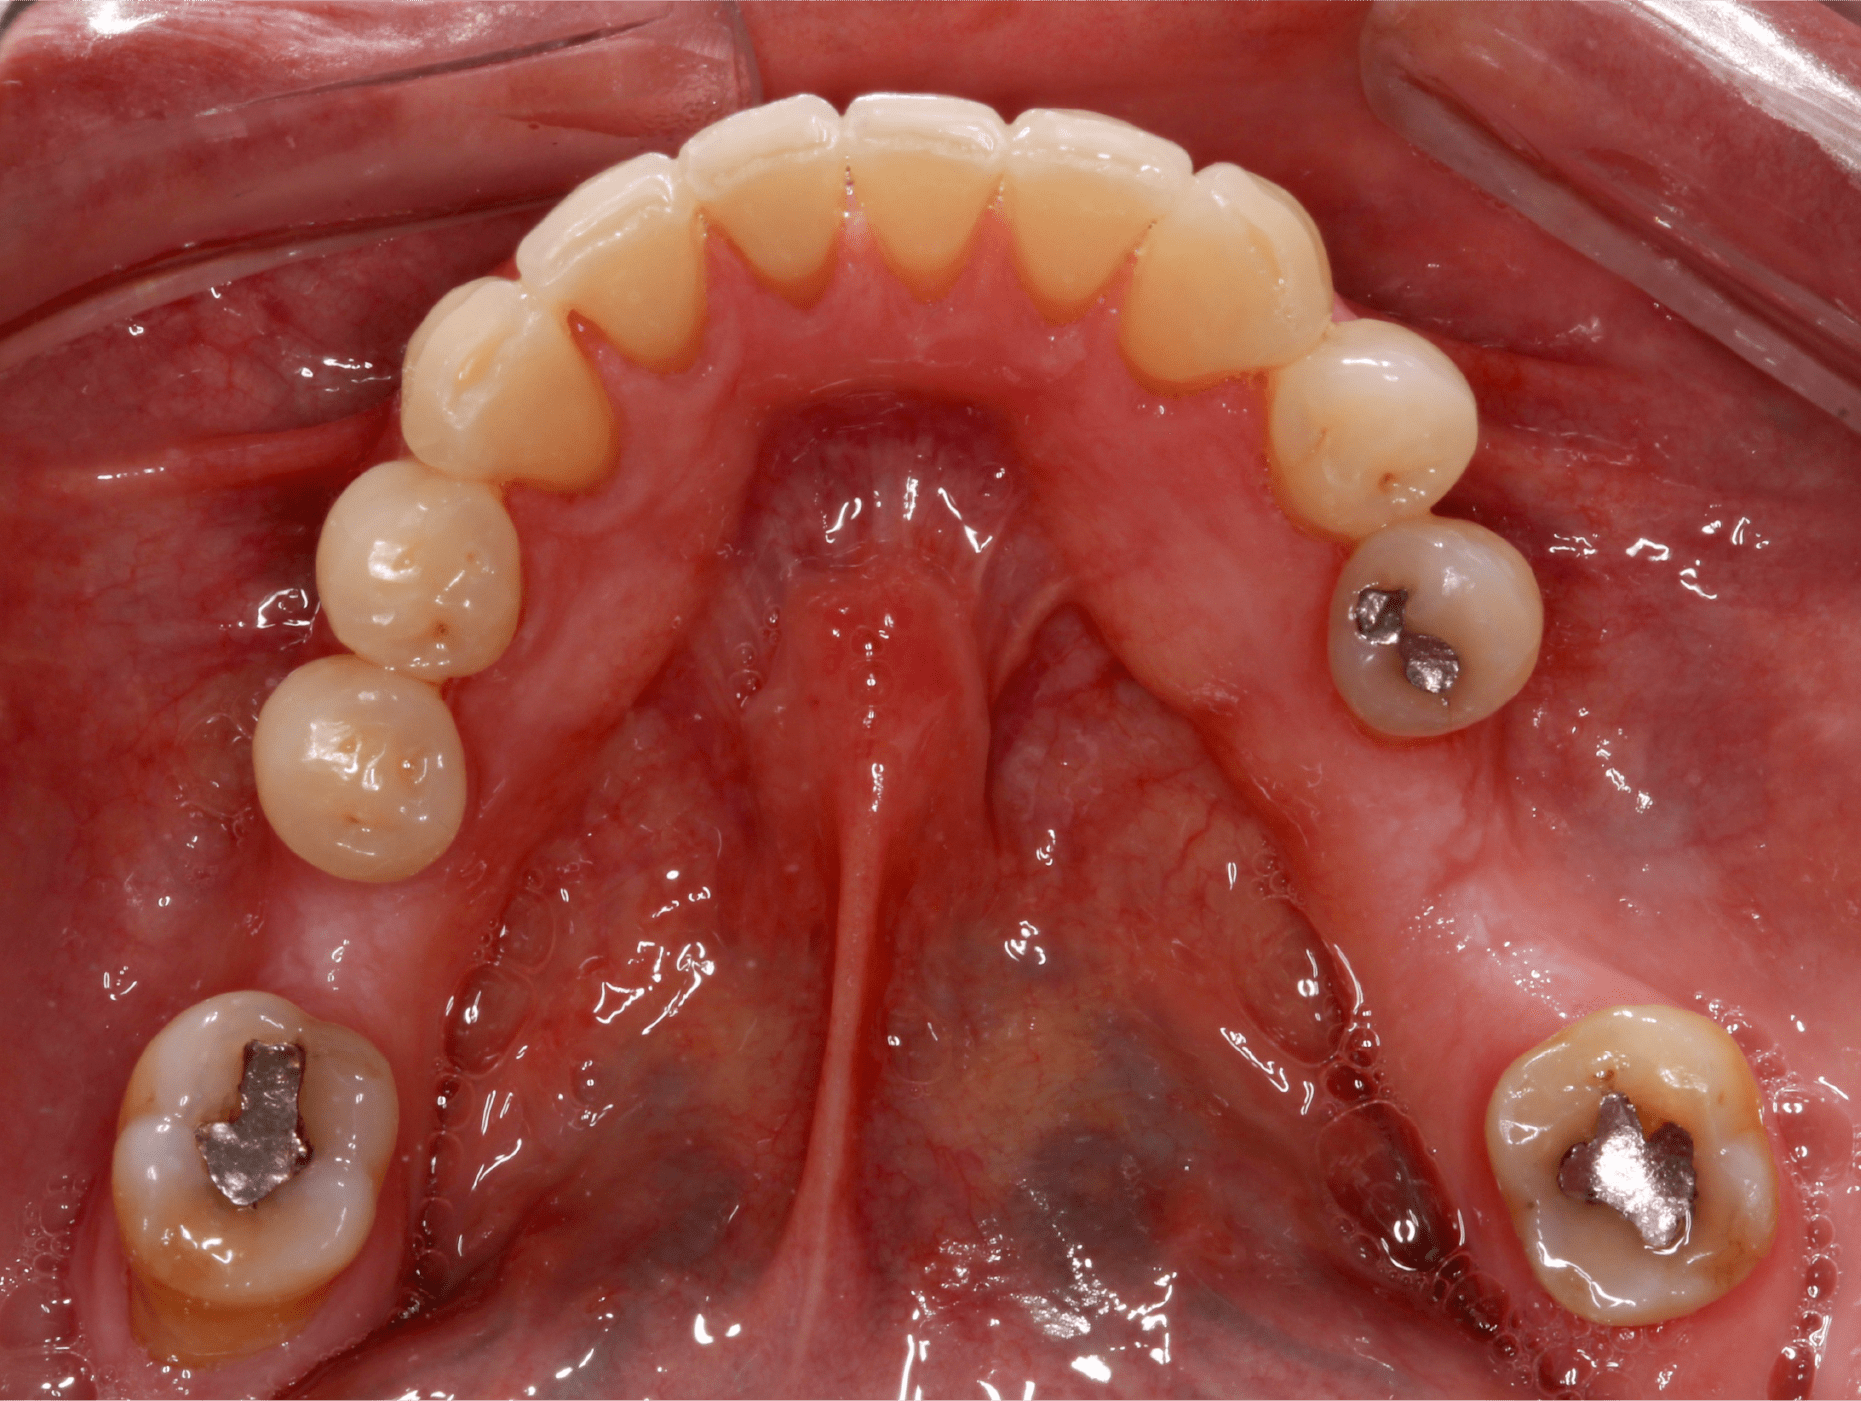

Paciente femenino de 57 años, ama de casa, originaria de Arandas, Jalisco se presenta al departamento de Periodoncia e Implantología derivada por el departamento de Prostodoncia. El motivo de su consulta fue “Quiero reponer mis dientes restantes” como resultado de la anamnesis presenta un buen estado de salud general aparente, sin antecedentes patológicos. (Fig. 1).

La examinación clínica reveló recesiones en múltiples órganos dentales y dos brechas edéntulas en la mandíbula correspondientes a los órganos dentales “36” y “46” las cuales fueron perdidas debido a caries (Fig. 2 y 3).

También se pudo apreciar que la paciente presentaba un fenotipo delgado y al medir la cantidad de encía queratinizada se observo una banda angosta de la misma, aproximadamente de 1 – 2 mm. (Fig. 4).

Fig. 1

Fig. 2